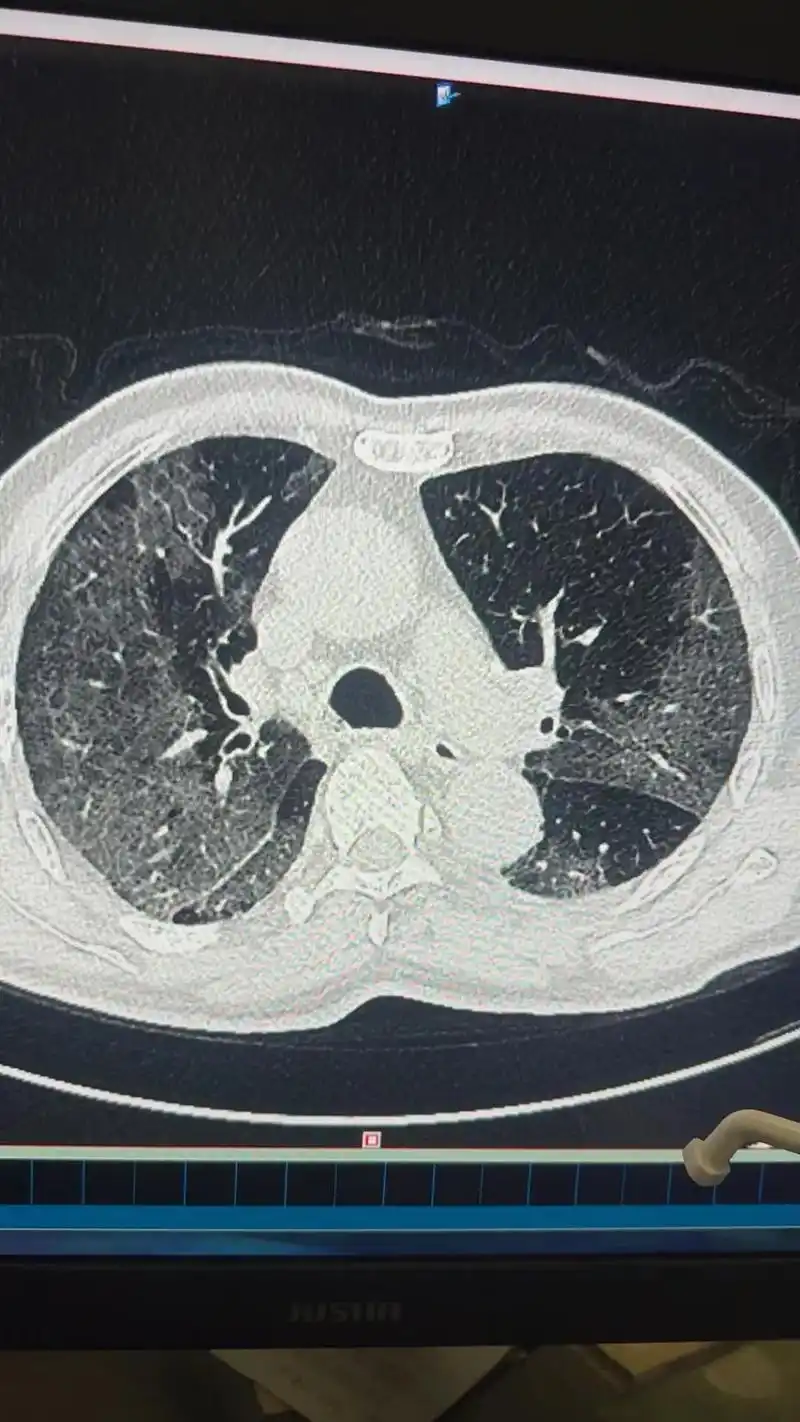

新冠肺炎治愈后多久复查新冠肺炎治愈后要复查几次

新冠肺炎并没走远 保佑大家百毒不侵 #这是我和进修老师 - 抖音